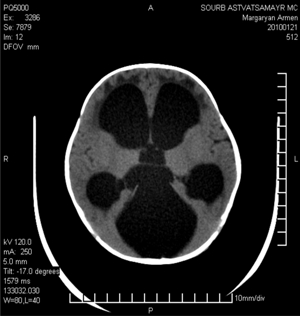

Были определены окклюзионные (у 92 больных) и сообщающиеся (у 114) формы гидро-цефалии посредством внутрижелудочкового контрастирования (рис. 2).

Рис. 2. Томограмма больного с окклюзионной тривентрикулярной гидроцефалией

Качественная оценка структур мозга оценивалась по следующим параметрам: наличию атрофии мозговой ткани, отека мозга, перивентрикулярного отека, уменьшению мозговой ткани, деформации и дислокации мозга, сужению субарахноидальных пространств и цистерн основания. Определялся градиент плотности мозговой ткани в зависимости от расстояния ликворных полостей, что дало возможность выявить участки пониженной плотности вокруг желудочков мозга (перивентрикулярный отек или свечение рис. 3).